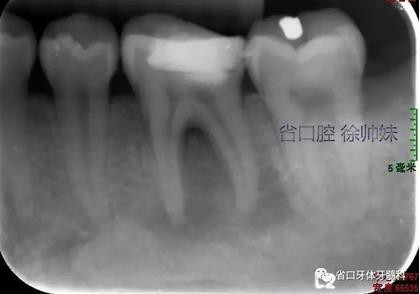

現(xiàn)病史:6個月前左下后牙區(qū)牙齦腫脹,反復溢膿,無明顯其他不適。4月前于我院牙體牙髓科(圖1)就診,診斷為“36牙周牙髓聯(lián)合病變”,建議試行36根管治療+牙周治療保留患牙,患者當時未行治療?,F(xiàn)再次來我院牙體牙髓科要求進一步診治。

圖1 術(shù)前4月的根尖片